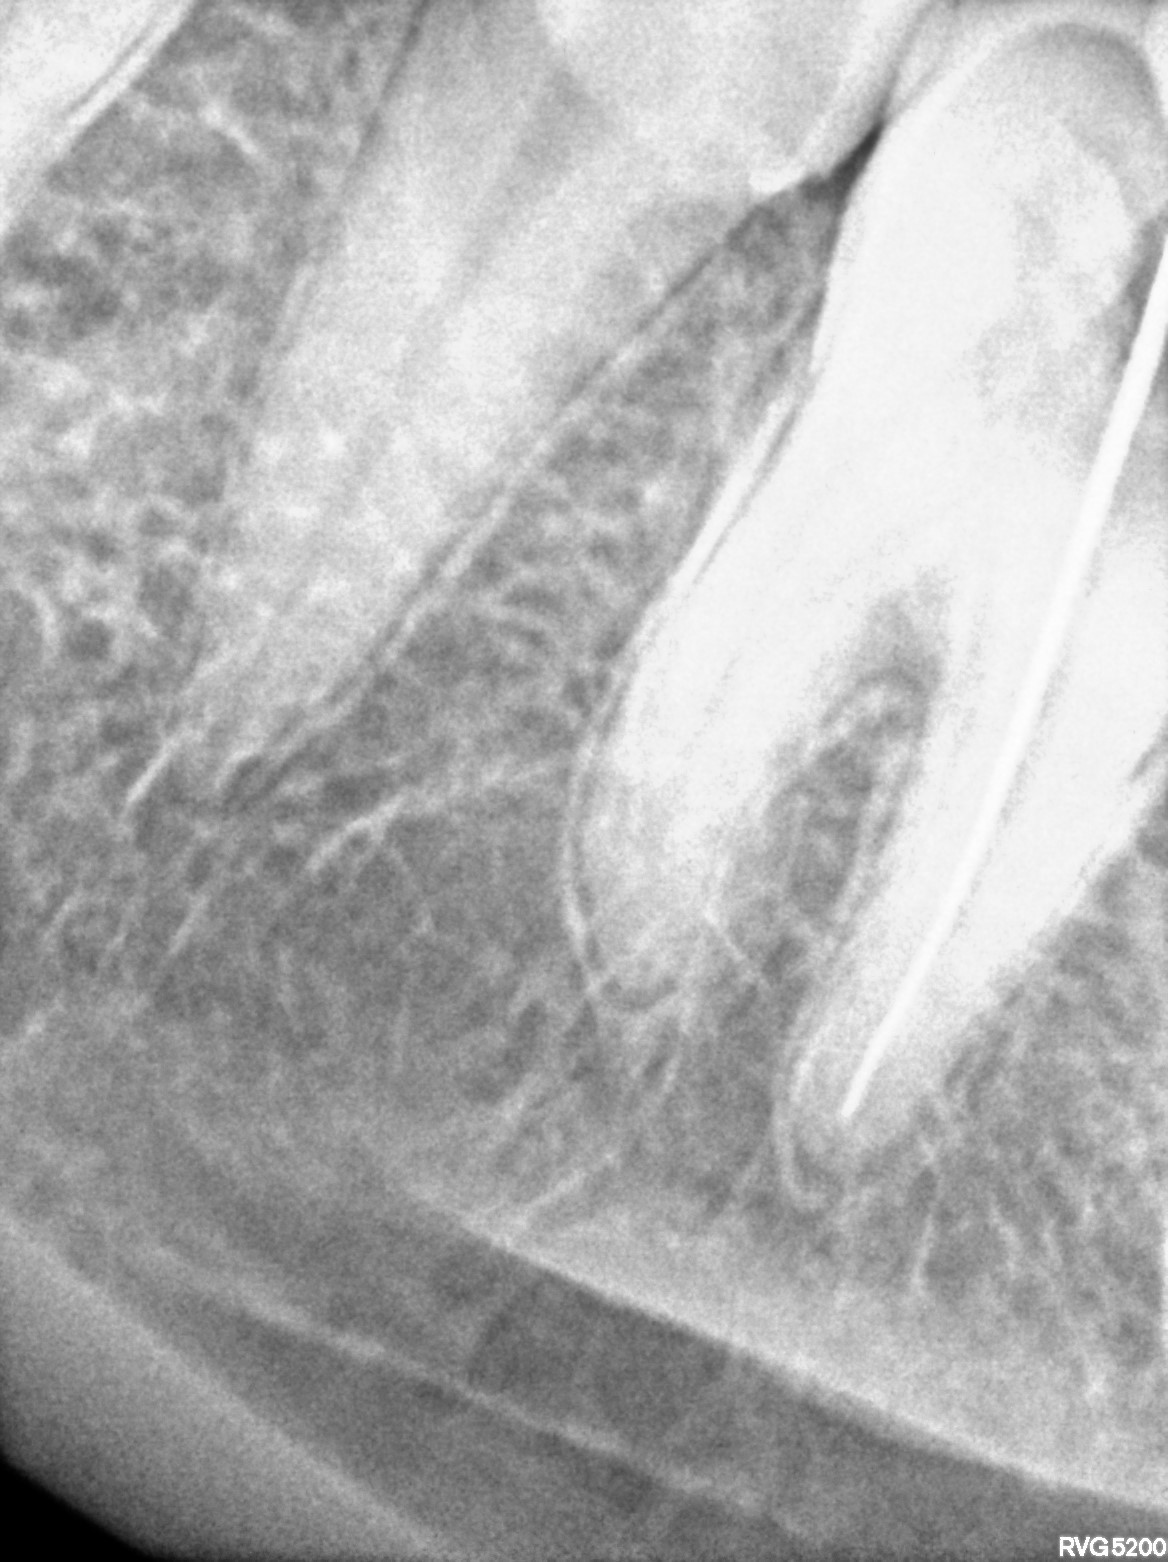

Dental Radiographs FHIR: DocumentReference · LOINC 24641-7

xray_1772180286_0.jpg

24641-7